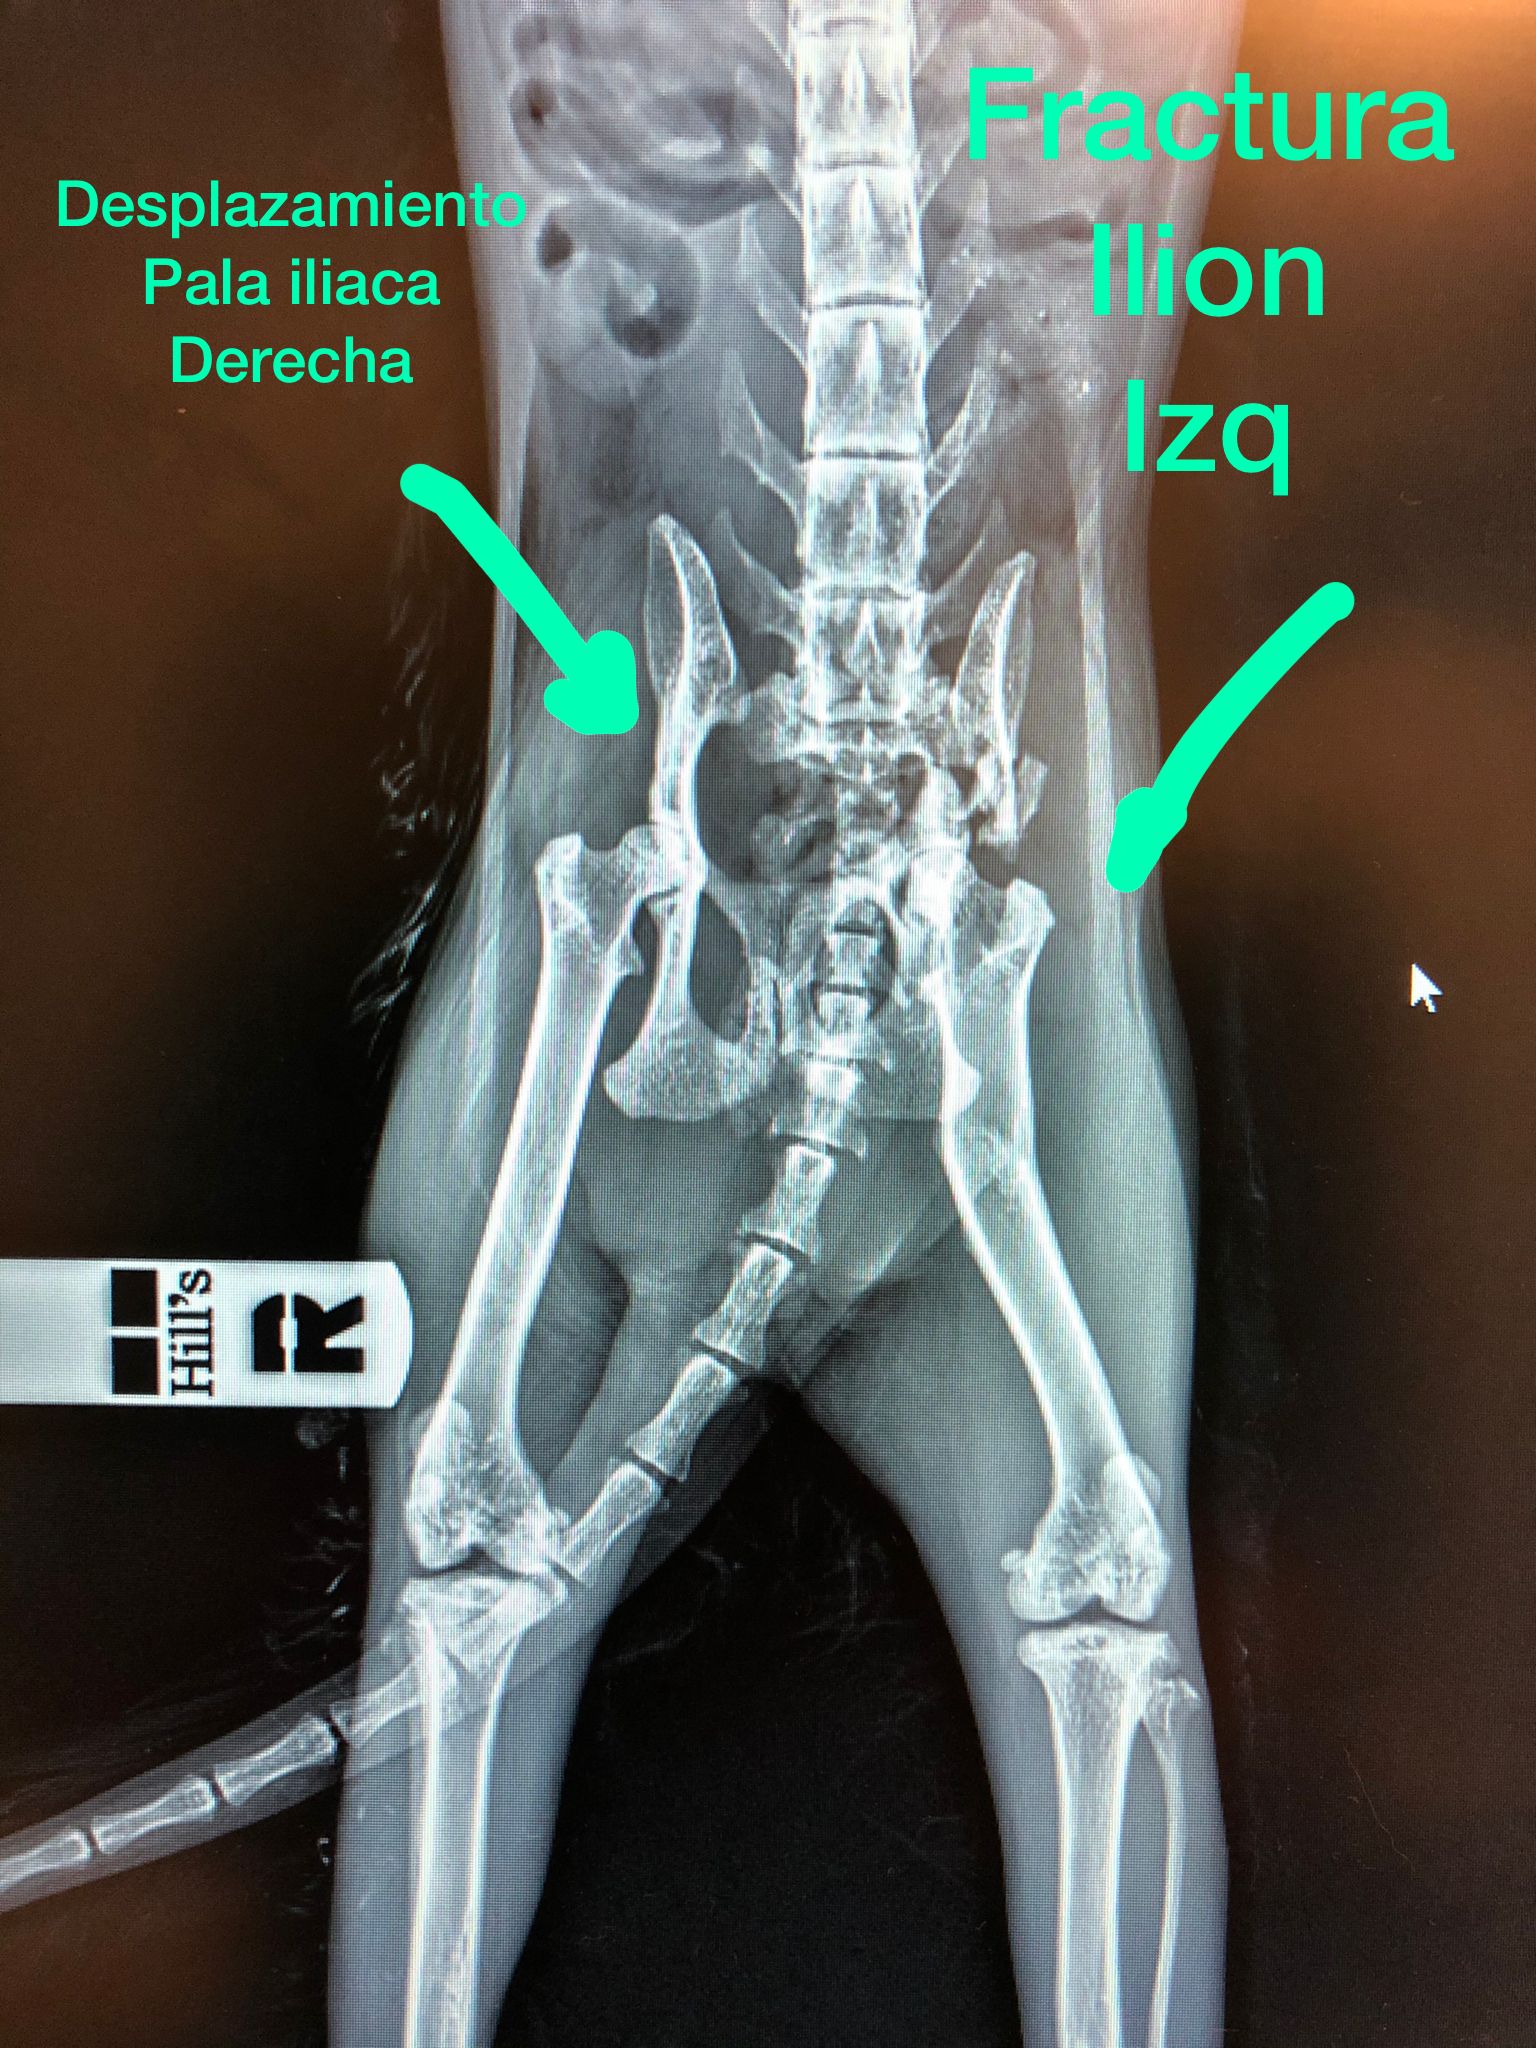

In May we received the traumatic news that a cat had run over, in the area of Avenida de Alicante, in Denia. PAMELA, as we named her, was found in a very bad condition. She had a broken hip and a displaced jaw. It was obvious that she was an older cat, which complicated everything even more.

Despite her injuries, keeping to our motto of doing all we can before we decide an animal is beyond help, we committed ourselves to help her, if she had the strength to survive (the treatments and necessary medical procedures). When a cat comes to us with bad injuries, we do not know if they are domestic or wild. The aftercare of a wild cat, who will not allow a human to treat them, or be near them, can mean disaster for a good recovery. Fortunately, Pamela is a very lovely cat, she endured us putting her through several surgeries, there were also many complications, but she did not give up. She even had to have a leg amputated so that she could walk better again. On several occasions we were on the verge of throwing in the towel and putting her to sleep ... but as she is a fighter, she kept going! Since coming into our care, she has been under the care and support of the Aliaga clinic in Moraira and La Marina in Denia, where she has been living all this time under the supervision of Ana, a passionate vet dedicated to animals, especially cats in need of help.